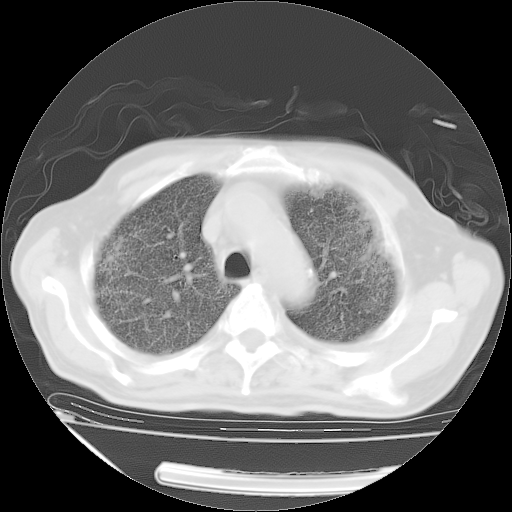

甲强龙80mg/日+抗结核治疗(异烟肼+利福霉素+乙胺丁醇)10天。复查肺部CT。

治疗10天肺部CT

94186 3 10.bmp

94186 3 11.bmp

94186 3 12.bmp

94186 3 13.bmp

94186 3 14.bmp

94186 3 15.bmp

94186 3 16.bmp

94186 3 17.bmp

94186 3 18.bmp

94186 3 19.bmp